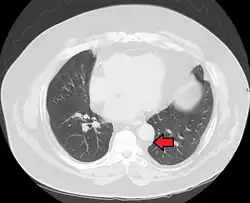

| Mediastinal lipomatosis | |